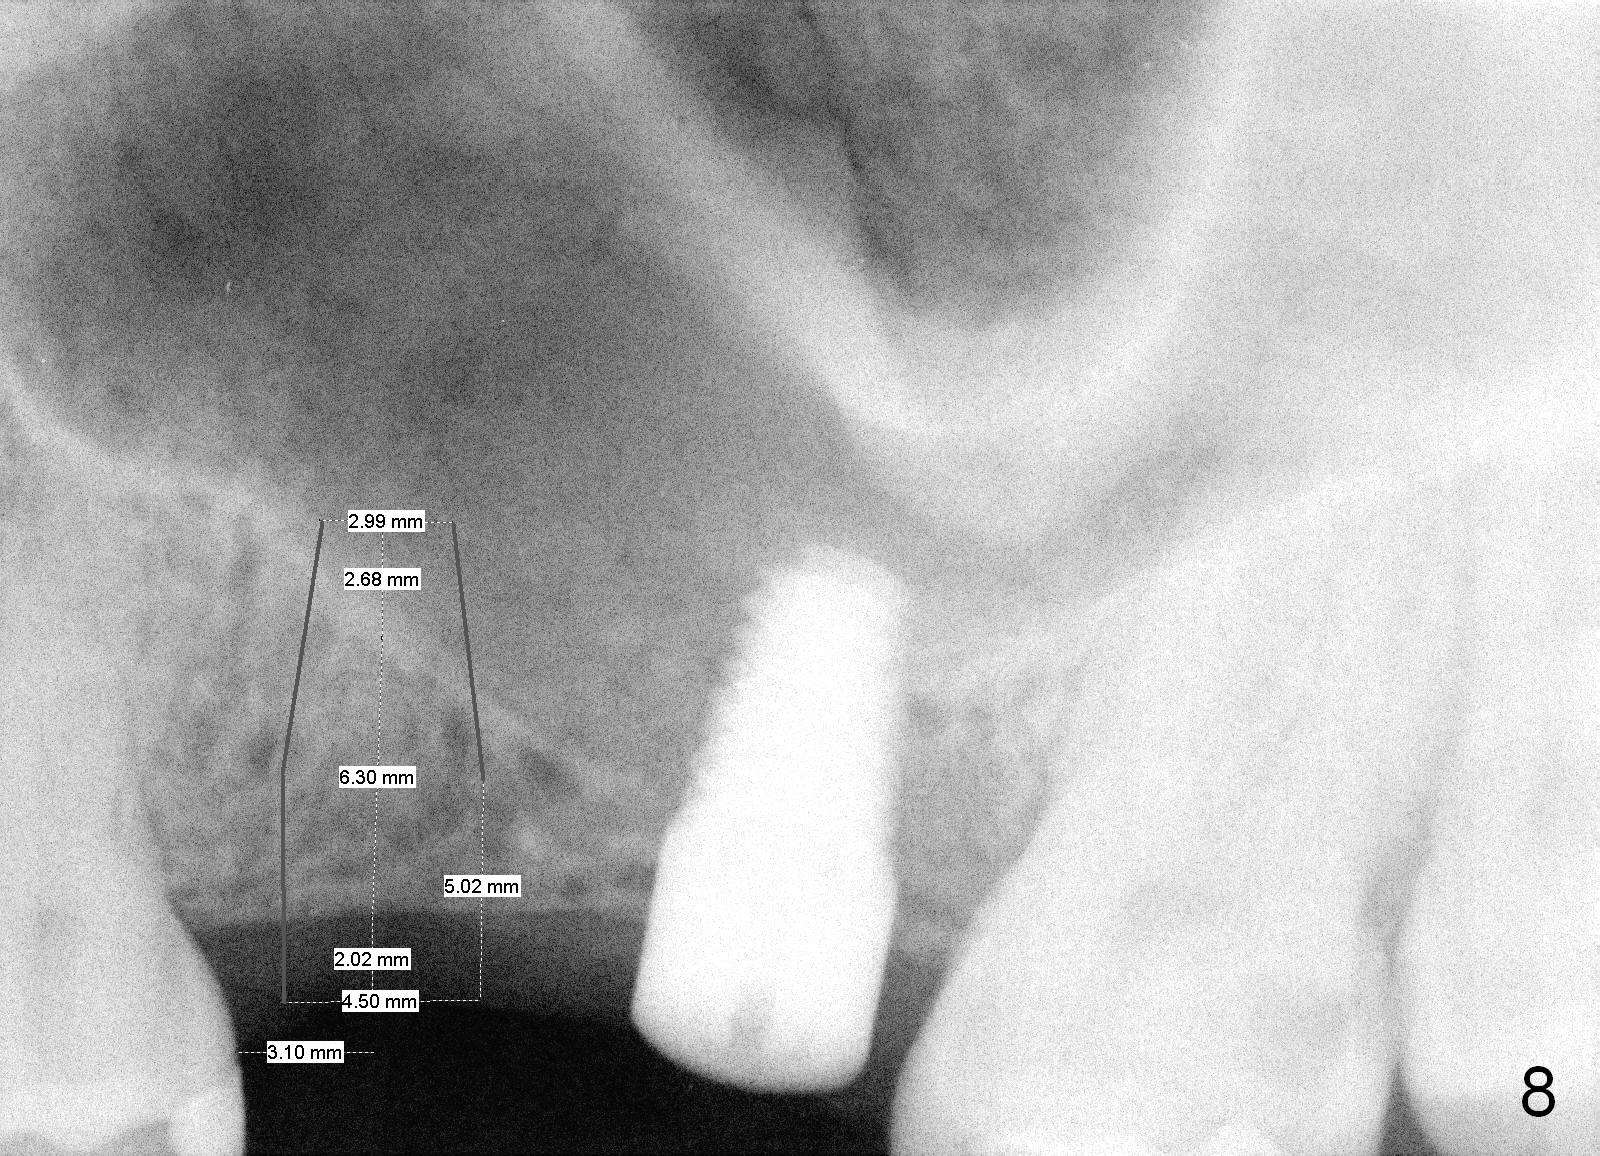

The patient returns for #13,14 implant placement. The ridge appears to be wide buccolingually (Fig.1 mirror view). A 4 mm tissue punch is used for access at the sites of #13 and 14. Osteotomy is initiated by using 3 mm trephine bur at the depth of 4 mm at both sites; 2 mm pilot drill is used to continue osteotomy at 8 mm deep at the site of #13. Sinus lift is accomplished by using tapered osteotomes 2,3 mm 6 mm deep, followed by 4.5x11 mm tap (Fig.2 T); 2 mm pilot drill (P) is reinserted into #13 osteotomy site with inadvertently penetrating the sinus floor. When the tap is removed from the site of #14, the sinus membrane is also found to be perforated. The sinus membrane at both sites is repaired by insertion of collagen dressing before bone graft. A 4x11 mm one-piece implant is placed at the site of #13 slowly hoping that it does not re-perforate the sinus membrane (Fig.3 O). Due to limited restorative height, the abutment portion of the one-piece is expected to be trimmed (Fig.4 O). In case of implant complication or failure, the implant may be difficult to be removed. Therefore the implant at the site of #14 is two piece one (Fig.4,5 I/A, 5x11 and 4x3 mm, respectively). The insertion torques for #13 and 14 are 35/40 and >60 Ncm. Immediate provisionals are canceled mainly because of patient's inability to open wide for long. Perio dressing is placed instead after adjustment of the height of the abutments. The patient experiences one episode of light nasal hemorrhage a few hours postop. Although the patient takes Amoxicillin for 1 week periop, the implant at the site of #13 dislodges 1 months postop (Fig.5). Immediate re-placement with a larger 2 piece one is canceled because of mild infection mesiobuccal to the implant at the site of #14 (Fig.6 >). Exploration around the latter implant reveals possible thread exposure in a small area. After copious irrigation with normal saline, Arestin is placed. Two months post exfoliation, the site is re-entered (Fig.7,8). There is a lingual defect. Osteotomy is initiated as buccal as possible. A 4.5x11 mm tapered tap penetrates the sinus floor without tearing the membrane (Fig.9). The same-sized implant is placed (25/30 Ncm) with sinus lift (Fig.10 *). The lingual defect is bone grafted. There is dehiscence lingually 7 days postop (Fig.11). Impression for final restoration is taken 1.5 months postop because of pending wedding. The crown has been in function for 2.5 months.